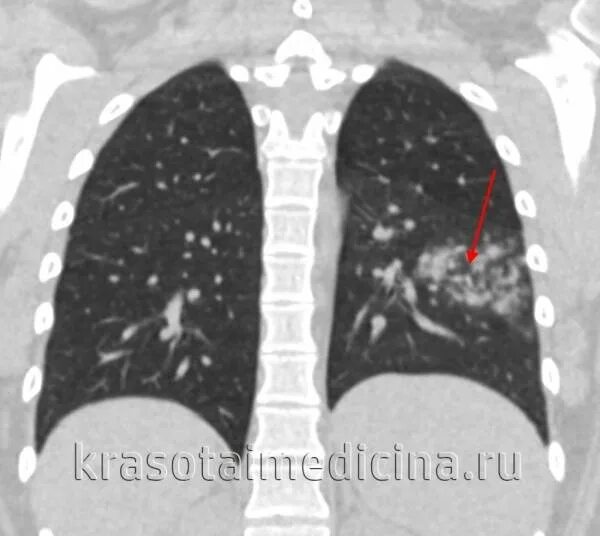

Сегментарная пневмония у взрослых что это значит